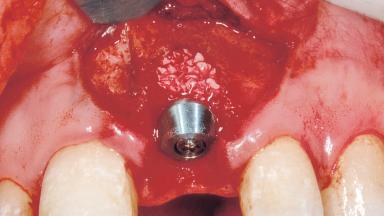

Immediate Placement of an Implant in a Maxillary Left Central Incisor Site

A 33-year-old female patient presented with an upper left central incisor that required extraction after a failed endodontic therapy. The tooth had been traumatized when the patient was a teenager and had undergone several endodontic treatments, including two apicectomy procedures. The patient was in good health and did not smoke. Clinical examination showed that the patient had a high lip line. In full smile, the gingival margins of the upper teeth were visible to the first molars. The gingival margins of central incisors 11 and 21 were only just showing. Examination of tooth 21 confirmed that the tooth was mobile and had hypererupted by 1 mm.

Placement Protocol Immediate implant placement

Tooth Site Maxillary incisor or canine

Socket Morphology Single-root socket

Socket Integrity Damage to one or more bone walls

Bone Volume Damage to one or more socket walls